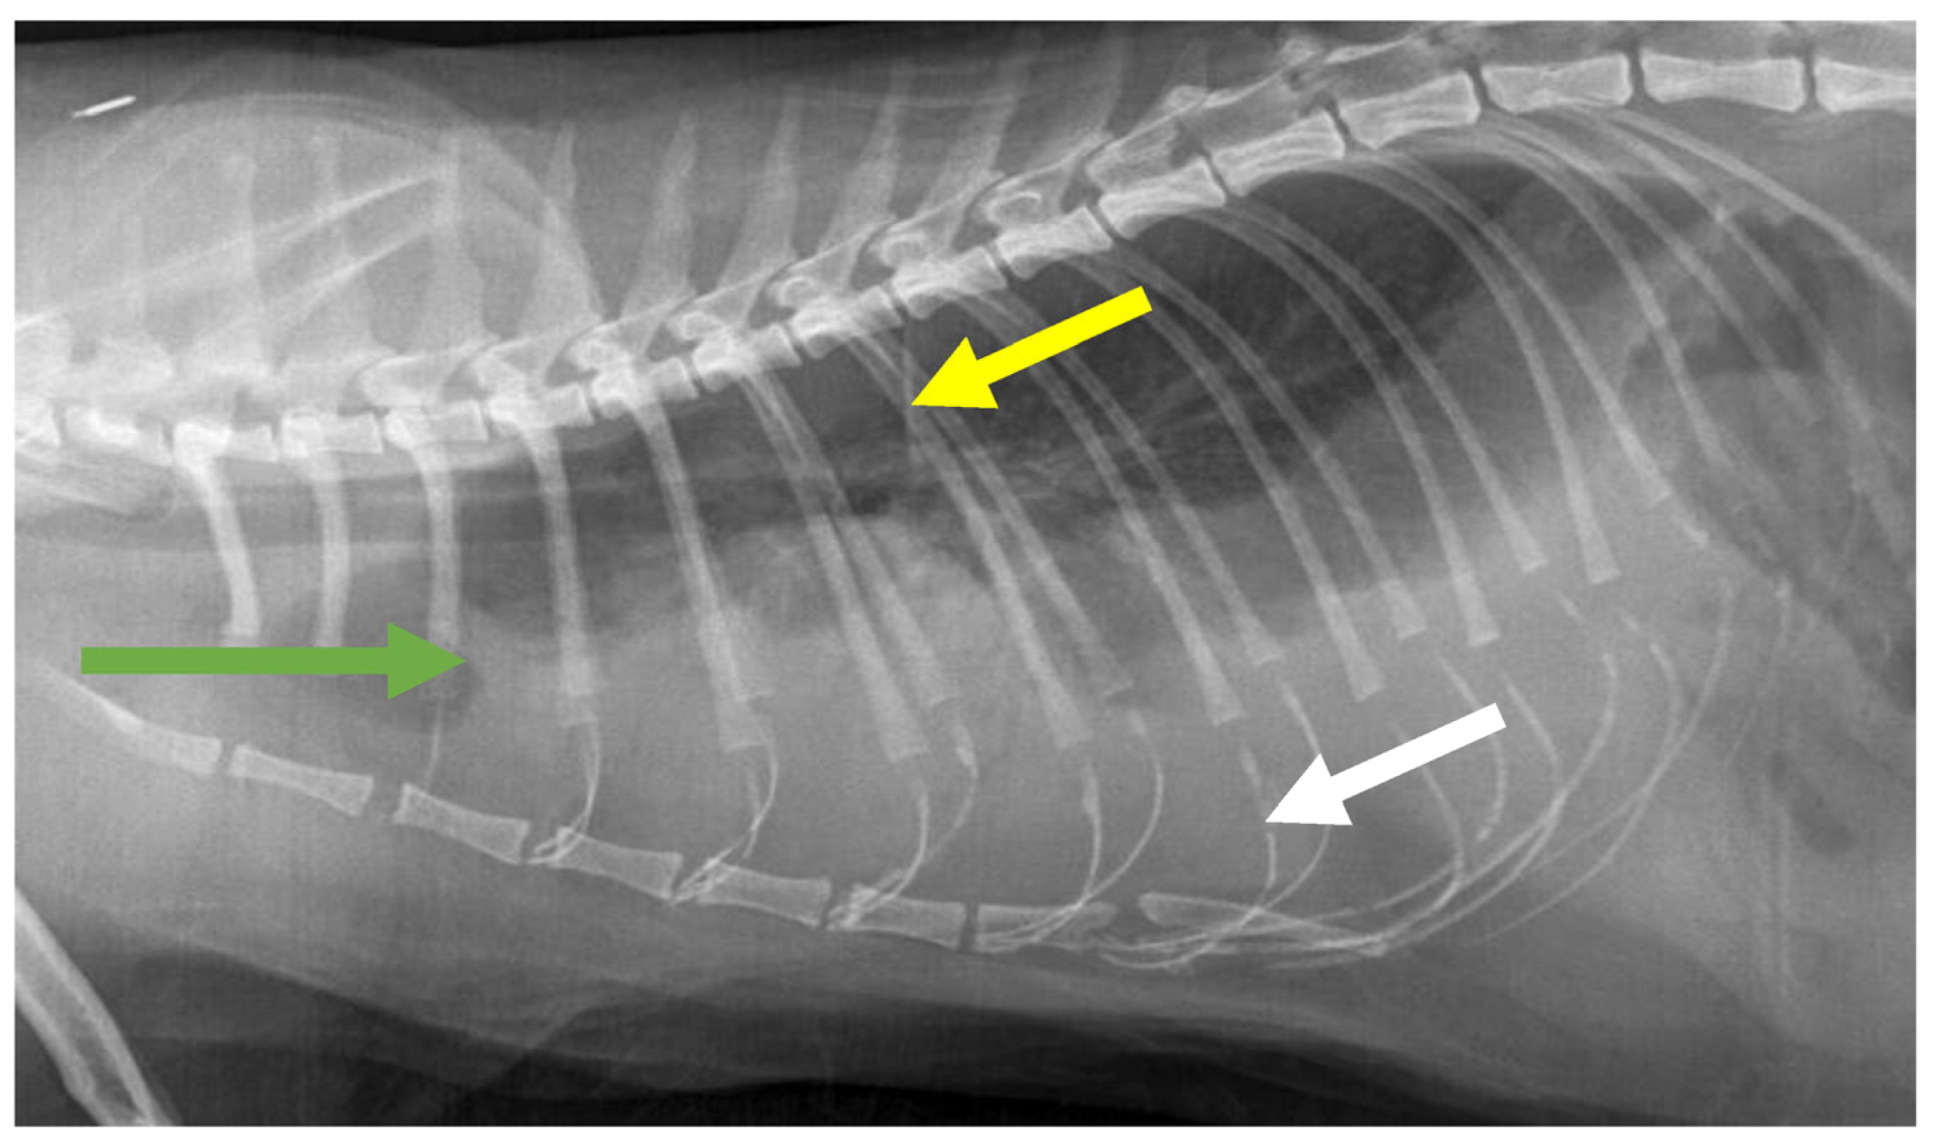

7.4. Diagnostic Imaging in FIP

7.4.1. Routine Imaging: Ultrasonographic and Radiographic Findings

7.4.2. Advanced Imaging of the CNS: MRI and CT